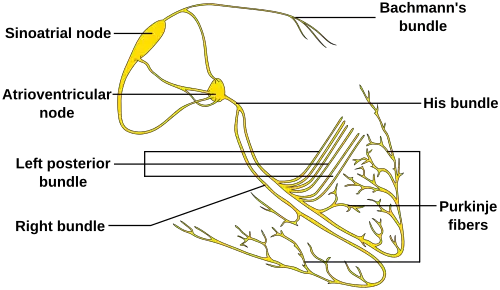

The human heart uses electrical signals to maintain and initiate the regular heartbeat in a living person. Conduction is initiated by the sinoatrial node ("sinus node" or "SA node"), and then travels to the atrioventricular node ("AV node") which also contains a secondary "pacemaker" that acts as a backup for the SA nodes, then to the bundle of His and then via the bundle branches to the point of the apex of the fascicular branches. Blockages are therefore classified based on where the blockage occurs – namely the SA node ("Sinoatrial block"), AV node ("AV block" or AVB), and at or below the bundle of His ("Intra-Hisian" or "Infra-Hisian block" respectively). Infra-Hisian blocks may occur at the left or right bundle branches ("bundle branch block") or the fascicles of the left bundle branch ("fascicular block" or "Hemiblock"). SA and AV node blocks are each divided into three degrees, with second-degree blocks being divided into two types (written either "type I" or "II" or "type 1" or "2"). The term "Wenckebach block" is also used for second-degree type 1 blocks of either the SA or AV node; in addition, second-degree blocks type 1 and 2 are also sometimes known as " Mobitz 1" and "Mobitz 2".

Following the path of the electrical signals, the places where conduction can be blocked give rise to different kinds of heart blocks:

| Location | Name |

|---|---|

| Within the sinoatrial node (SA node or Sinus node), where the heart's signals originate | Sinoatrial nodal blocks (often abbreviated "SA nodal block" or "SA block", sometimes written "Sinuatrial block") |

| Within the atrioventricular node (AV node) | Atrioventricular block (often abbreviated "AV nodal block", "AV block" or AVB). |

| At and below the bundle of His | Intra-Hisian blocks and Infra-Hisian blocks respectively. |

| Within the left or right bundle branches | Bundle branch blocks. |

| Within the fascicles of the left bundle branch | "Fascicular block" or hemiblocks. |